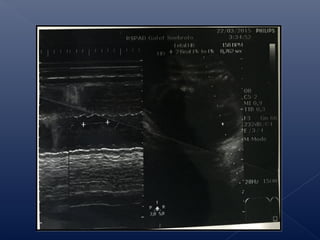

 Janin : Tunggal, Presentasi kepala

 Plasenta : di korpus belakang kanan, jauh dari OUI

 Amnion : Normal (Single Pocket 3)

 Gerak Janin : Normal

 Biometri : Sesuai kehamilan 36 minggu

Biparietal diameter : 92.4mm

Head circumference : 32.3mm

Abdominal circumference : 309mm

Femur diaphysis length : 67.8mm

EFW : 2598 gram

USG Trimester 3 (22 Maret 2015)

 Jantung : HR 158 dpm

 Anomali : Tidak tampak anomali mayor

 Lain-lain : Tidak tampak gambaran tali pusat di

leher

 Penilaian : janin presentasi kepala tunggal hidup,

biometri sesuai kehamilan 36 minggu, ketuban

cukup